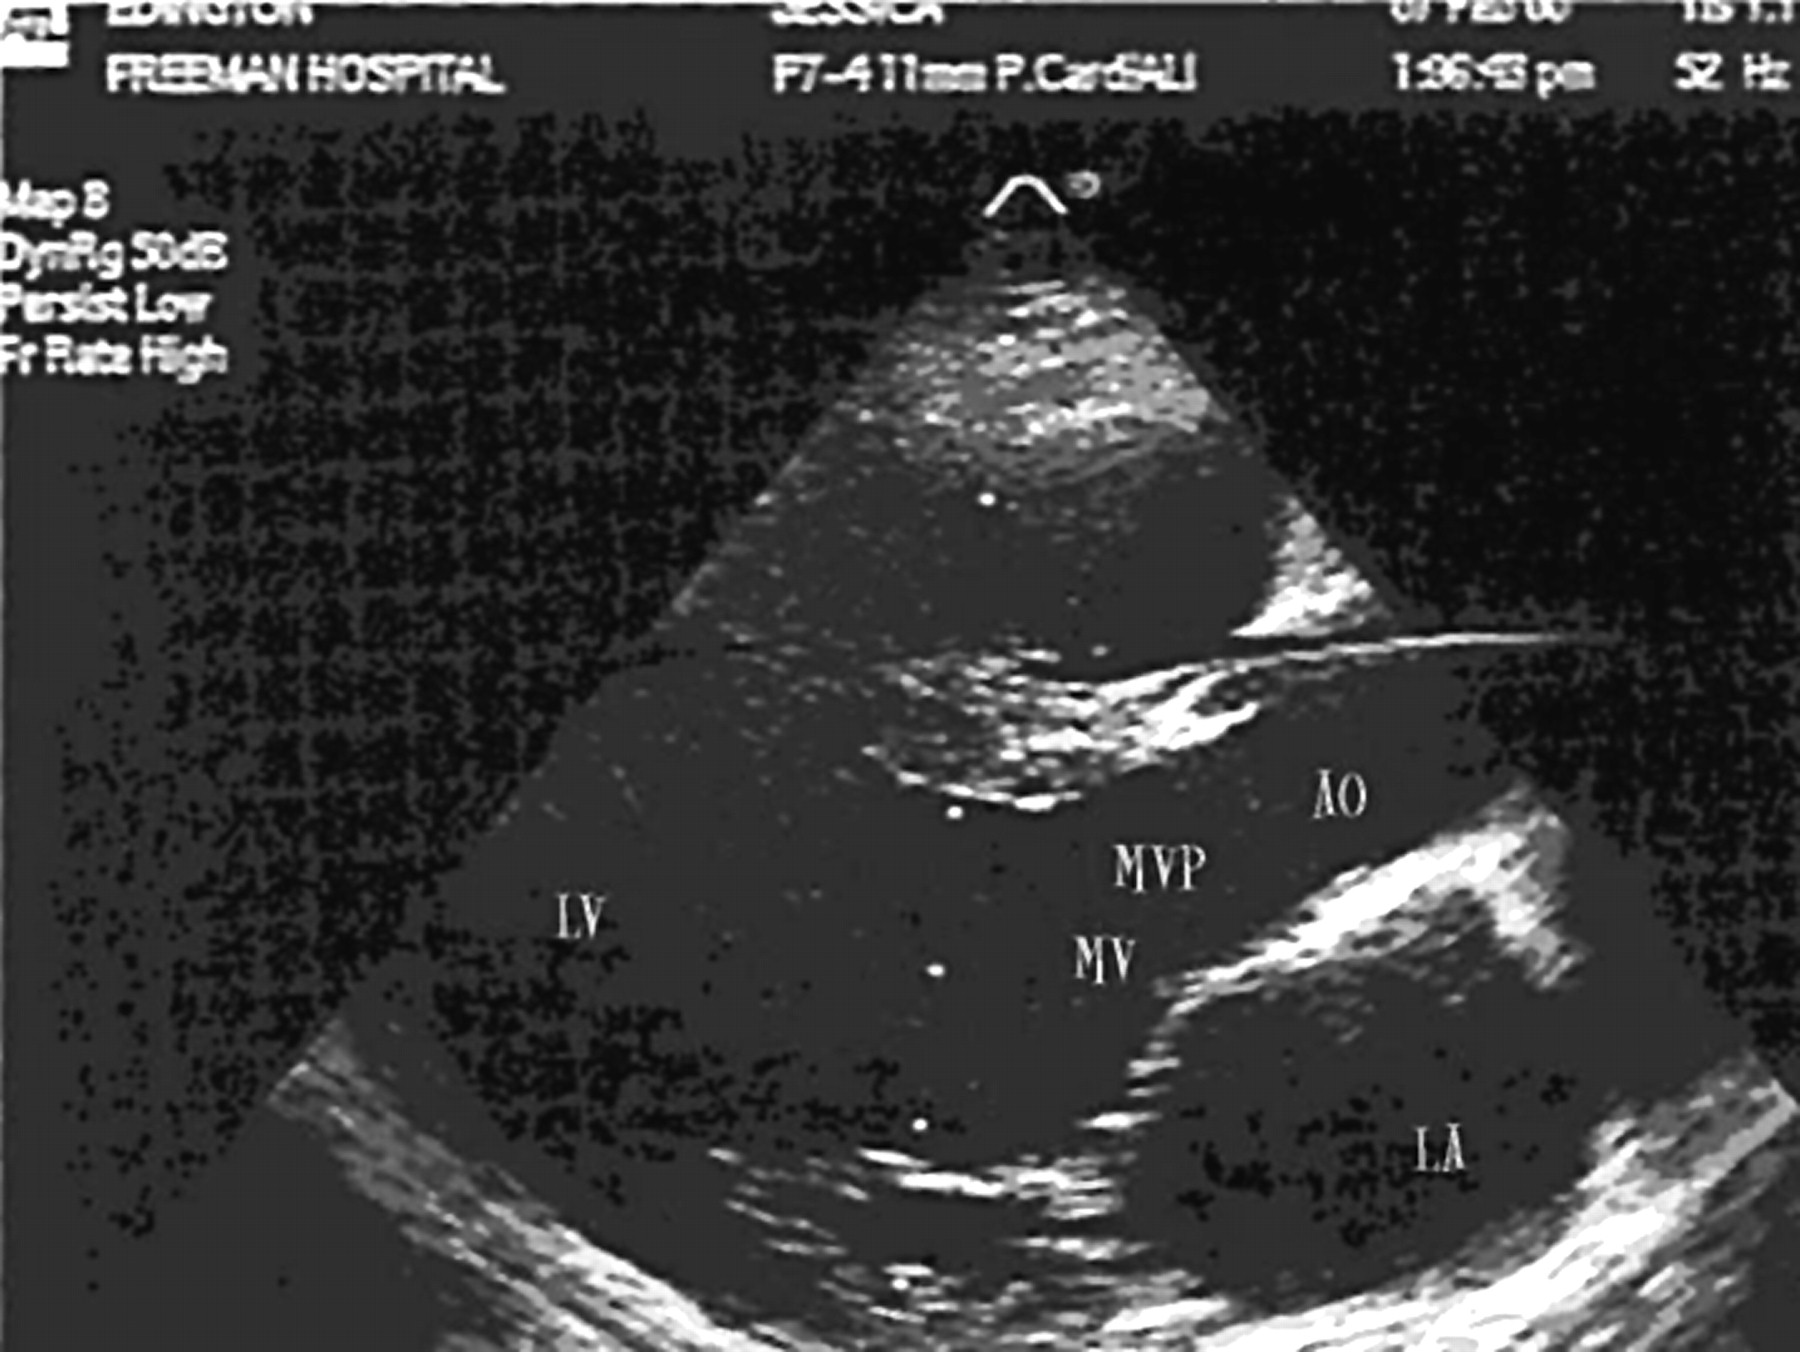

Leaking Mitral Valve

Leaking Mitral Valve Is A Leaking Heart Valve Bad The importance of tracking heart valve disease symptoms. The outlook for someone with a leaking heart valve depends on which valve is affected and the severity of the regurgitation. Sometimes, blood moves backward through a valve. A leaky heart valve may not cause any symptoms, or symptoms can come on gradually over time. Recognizing the symptoms of worsening heart valve. Is A Leaking Heart Valve Bad.